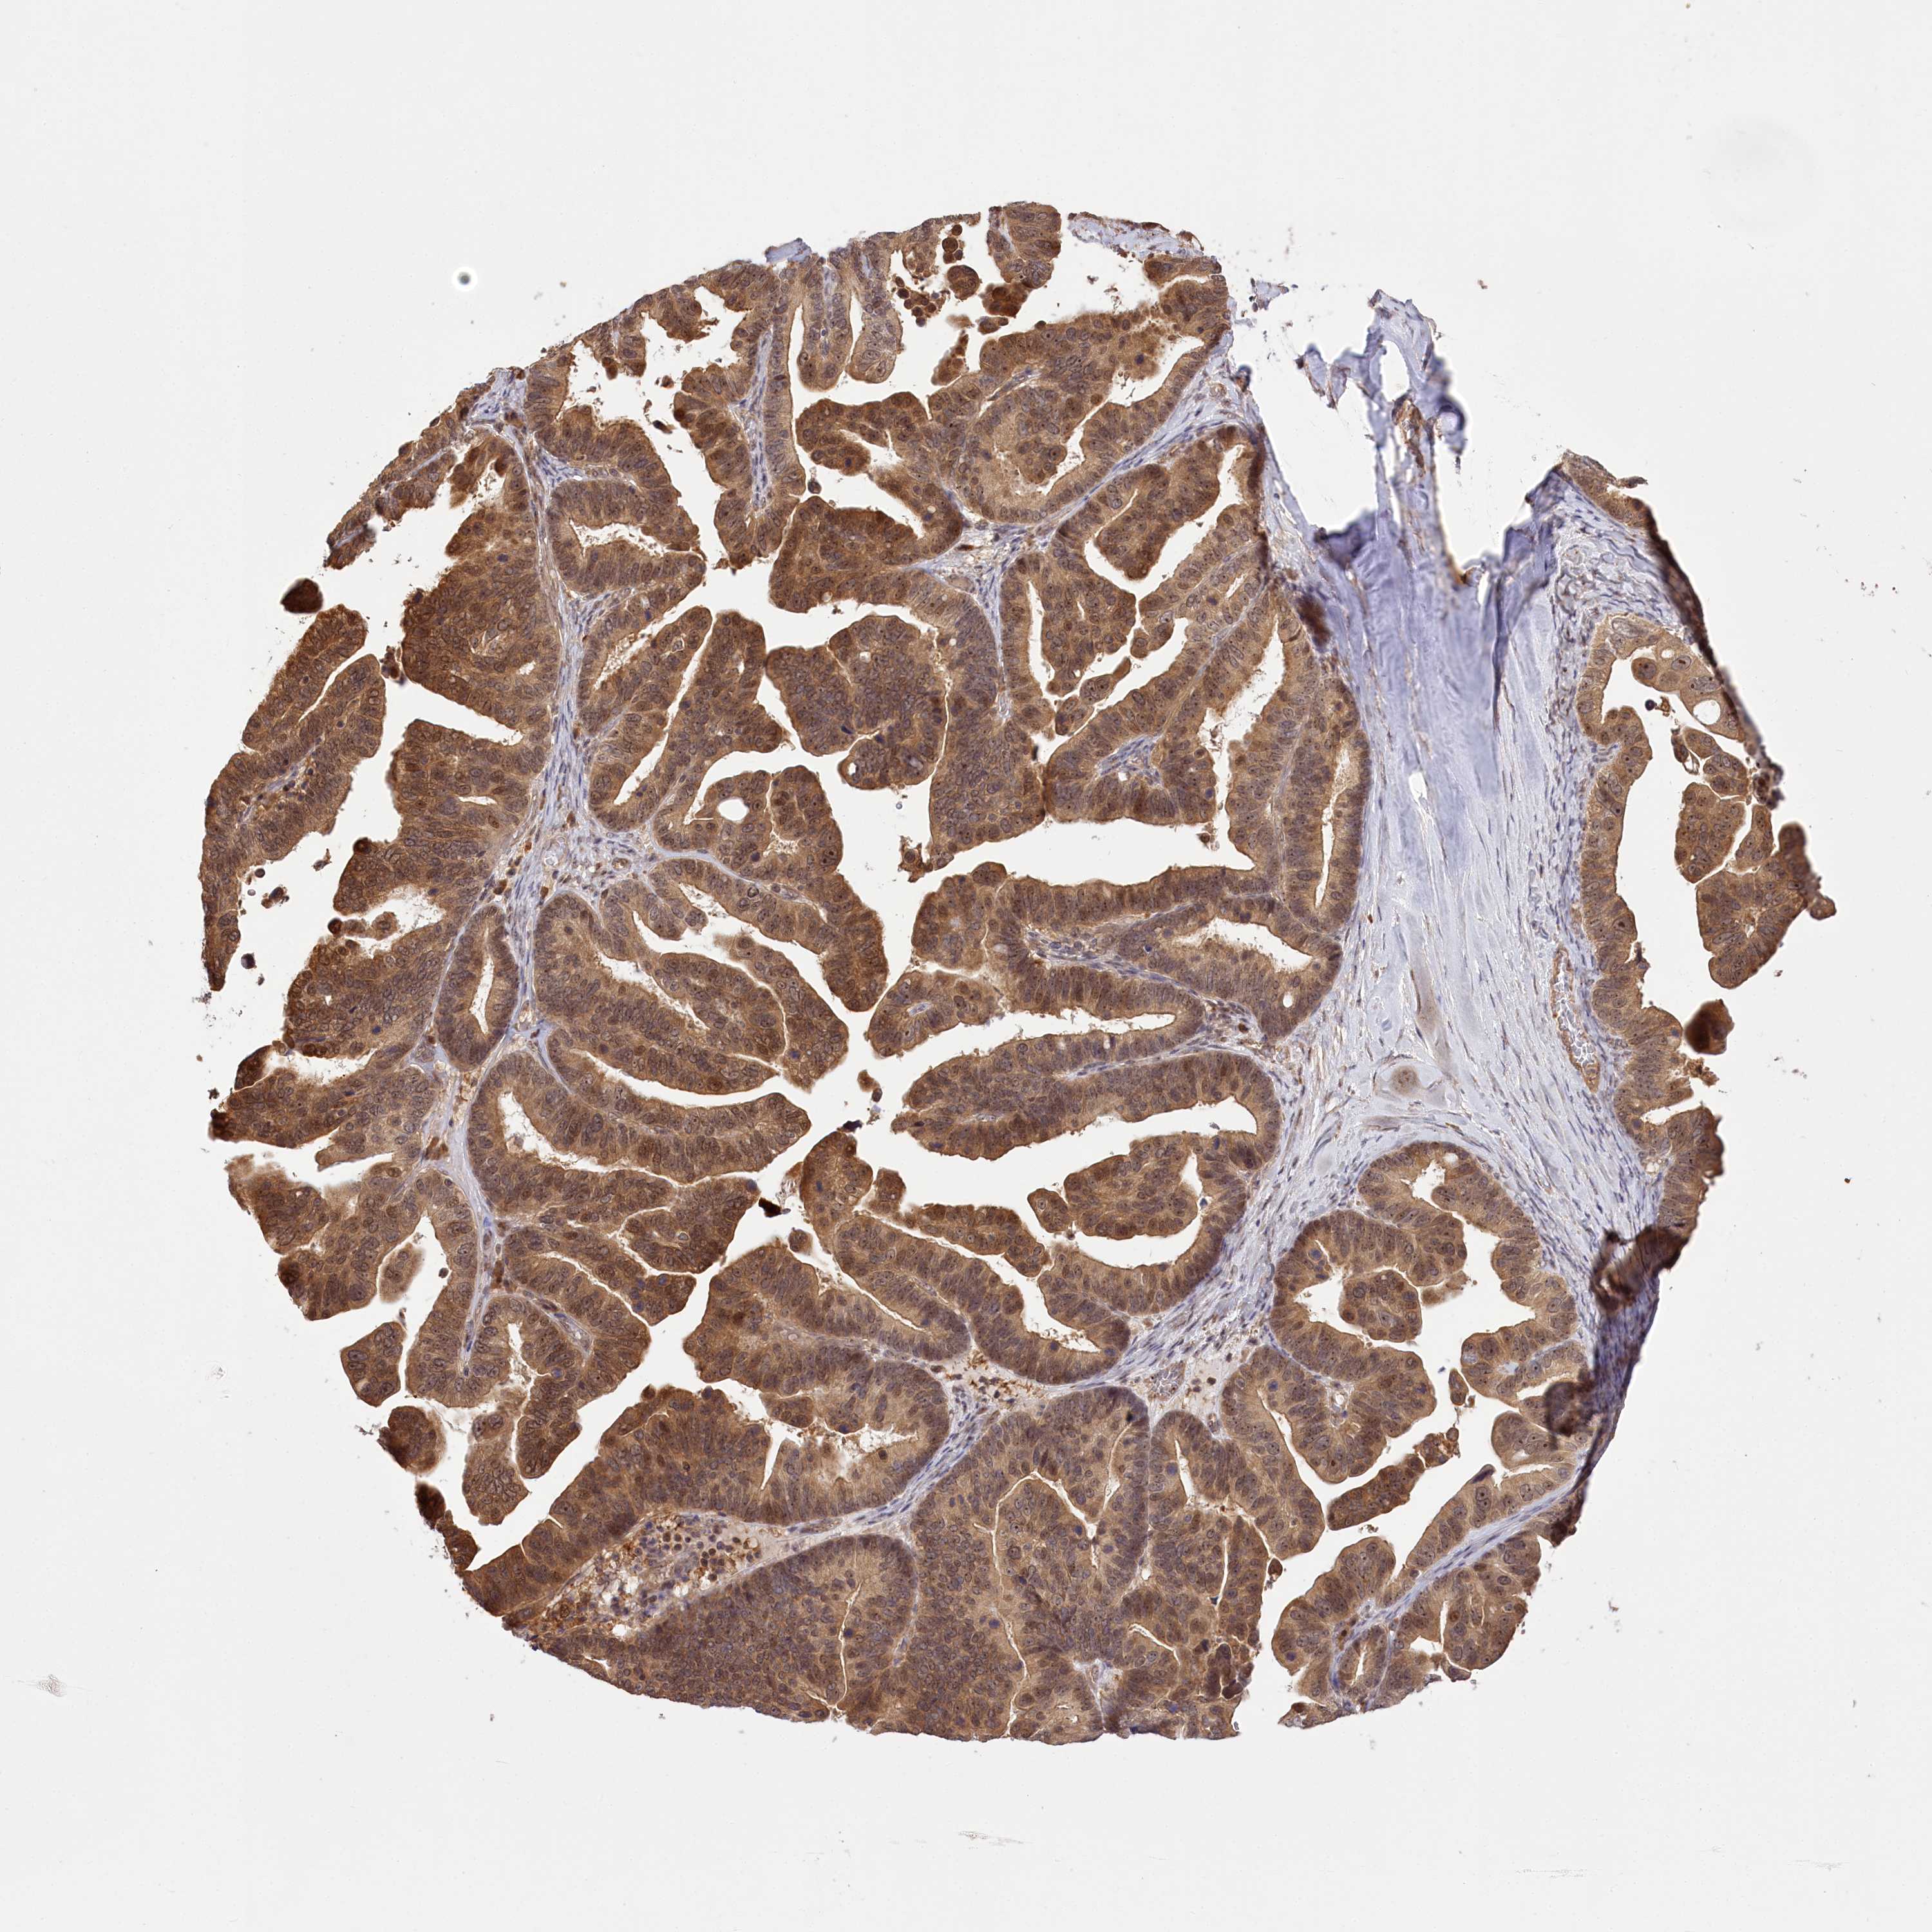

OVARIAN CANCER - Protein expressioni

A mouse-over function shows sample information and annotation data. Click on an image to view it in a full screen mode. Samples can be filtered based on level of antibody staining by selecting one or several of the following categories: high, medium, low and not detected. The assay and annotation is described here.

Note that samples used for immunohistochemistry by the Human Protein Atlas do not correspond to samples in the TCGA dataset.

Antibody stainingi

Antibody staining in the annotated cell types in the current human tissue is reported as not detected, low, medium, or high, based on conventional immunohistochemistry profiling in selected tissues. This score is based on the combination of the staining intensity and fraction of stained cells.

Each image is clickable and will lead to virtual microscopy that enables deeper exploration of all samples and also displays staining intensity scores, fraction scores and subcellular localization as well as patient and tissue information for each sample.

Antibody HPA037811

Antibody HPA037812

Staining

High

Medium

Low

Not detected

Intensity

Strong

Moderate

Weak

Negative

Quantity

>75%

75%-25%

<25%

None

Location

Nuclear

Cytoplasmic/membranous

Cytoplasmic/membranous,nuclear

Cystadenocarcinoma, serous, NOS